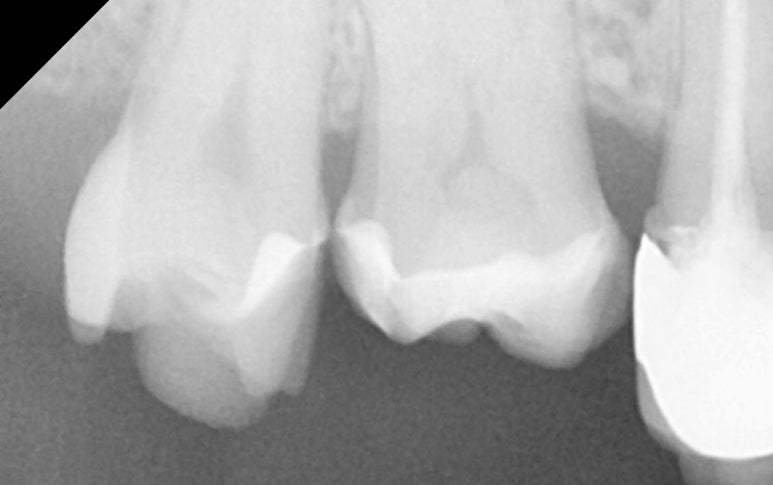

25.11.11 #17 치아의 금 인레이가 탈락하고 충치가 발생한 모습.

금 인레이가 왜 떨어졌는지 확인해보니

안타깝게도 인레이 하방으로 2차 충치가 진행되어 있었고,

그 영향으로 치아 일부분도 깨져나간(파절) 상태였습니다.

25.11.11 레진 코팅 후 엑스레이 사진

25.11.19 접착 후 엑스레이